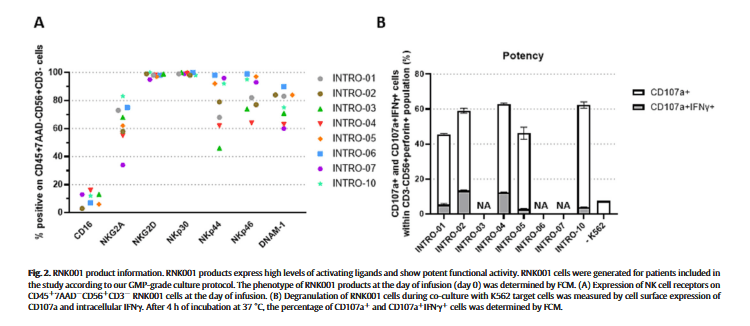

最终,7名患者接受了RNK001治疗:6名未接受Cy/Flu调理,1名接受Cy/Flue调理(图1B)。表1显示了RNK001制造的患者特征及其各自的UCB供体。尽管腹膜癌症指数(PCI)[28]最初并不被视为合格标准,但我们在治疗了第一组(INTRO-01、03和04)中的三名患者后修订了方案,并将36例患者中超过15例的PCI阈值作为排除标准。所有纳入患者的经皮冠状动脉介入治疗中位数为12.5(范围3-26;表1)。所有患者的Karnofsky评分均在80至100之间。在第二组中,一名患者在接受Cy/Flu化疗后接受了RNK001治疗,该患者耐受良好,没有严重毒性。

7名患者服用了RNK001产品,所有患者均完成了IL-2输注。RNK001输注耐受良好,无NK细胞输注相关毒性。